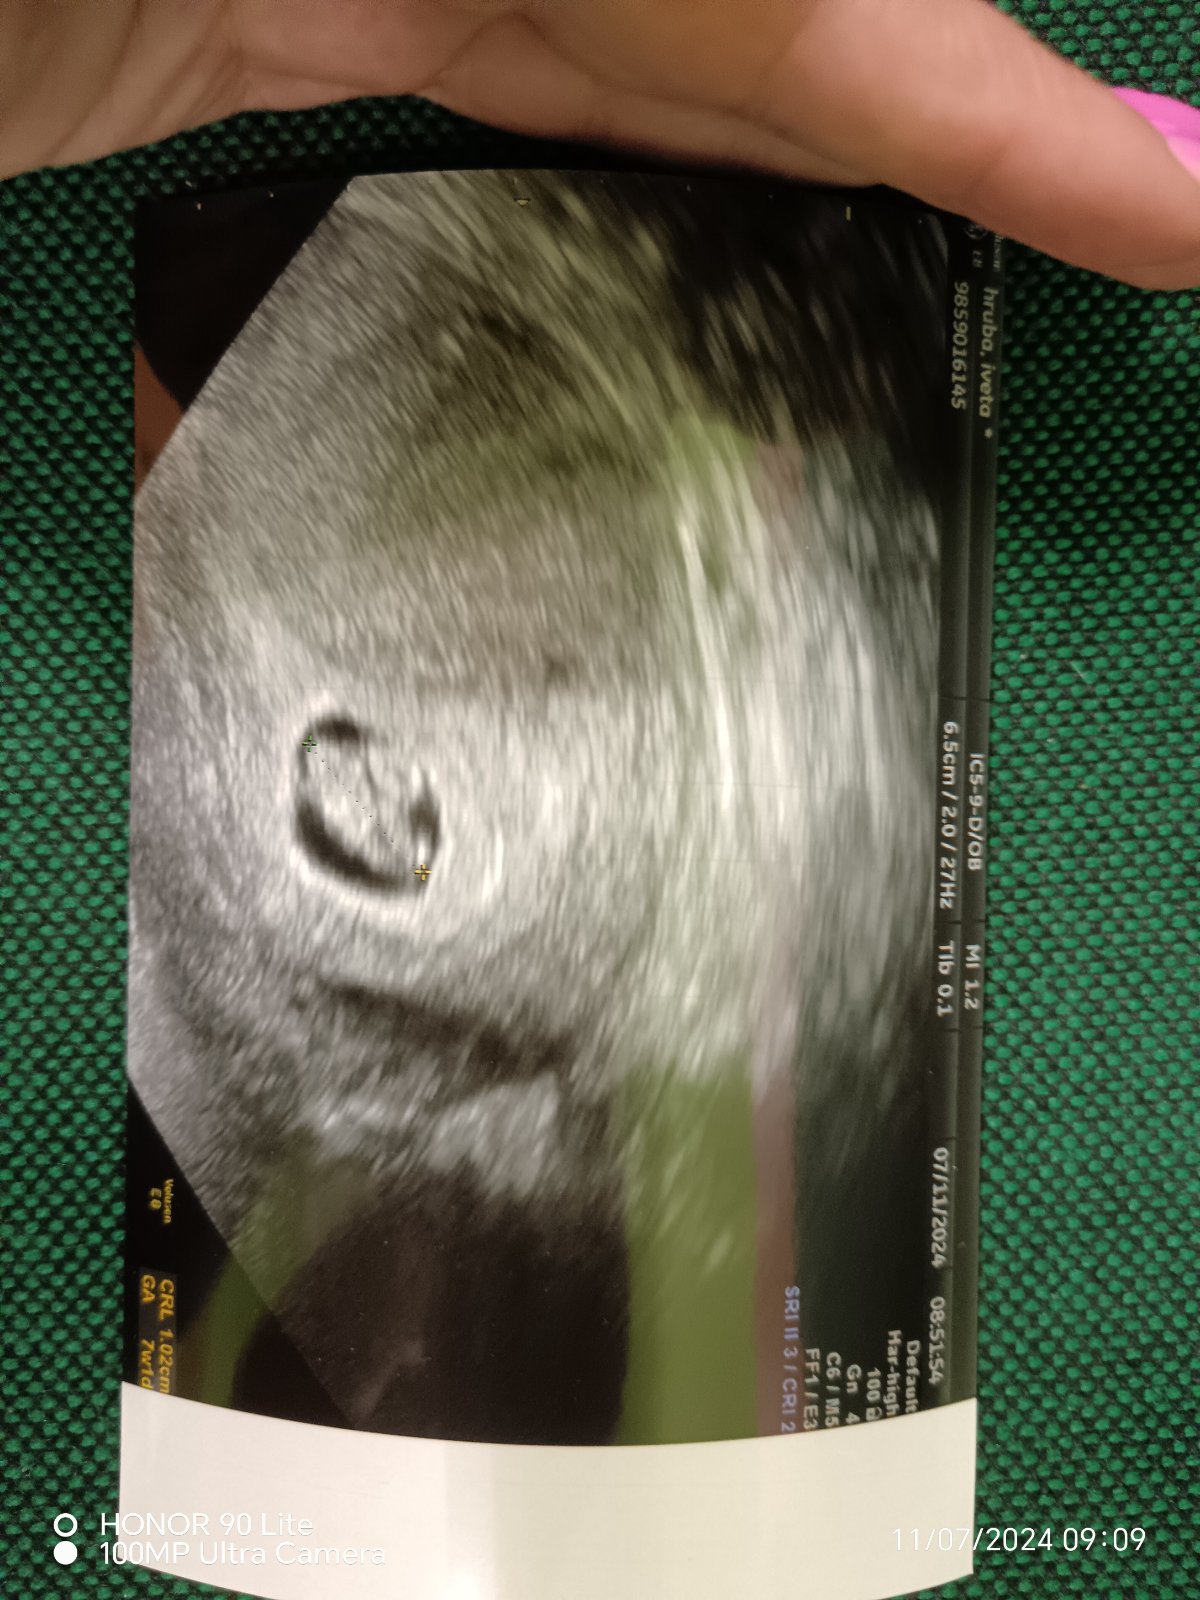

Je mi 25 let a už mám po mimoděložním 🤦♀️ a přišla jsem o jeden vejcovod. Takže samozřejmě, že sace n otěhotnění je, ale trošičku ztíženější. Oba s přítelem chceme mimo, ale on se zatím drží pevné nohama na zemi a snaží se mě krotit abych pak nebyla zklamaná. Ale příznaky některé mám, bývá mi zle, jsem neskutečně opupinkovaná a nasere mě kde co 😅 nedalo mi to a udělala jsem si testy. Jelikož mám nepravidelný cyklus, tak jen podle příznaků tuším ovulaci... A cca podle toho i délku cyklu. Takže jsem si dělala testy 2 dny před cca očekávanou MS a dneska kdy se měla dostavit a nedostavila. A nejprve ty dva dny byl úplně slaboulinký duch a dneska je o dost zřetelnější ale není to ještě čárka s jistotou.

@ivetulilinka gratuluji 😘